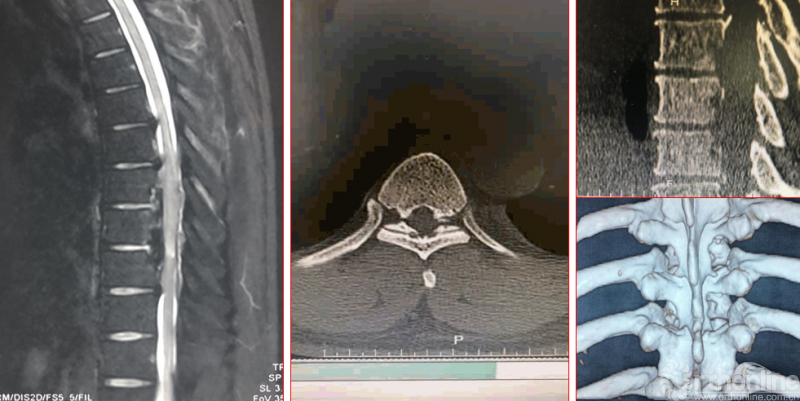

术前资料

术后影像学资料

术后第二天资料